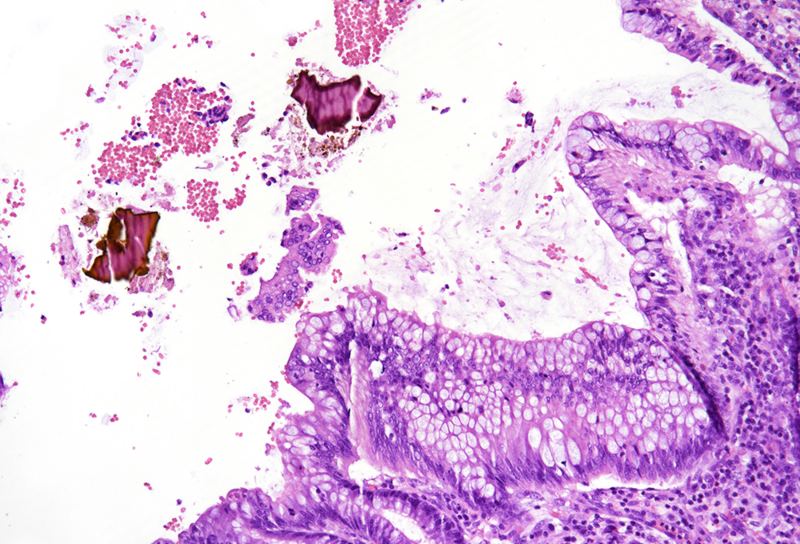

On macroscopy, multiple ulcers were visible on the mucosa of the colon. Histology showed ulcers with prominent granulation tissue, reaching the muscular wall of the bowel. They were surrounded by colonic mucosa with regenerative architectural changes (Panels A-B). In the ulcers and on the surface mucosa, yellow-pink polygonal foreign material with scale-like appearance was seen, which corresponded to the given sevelamer drug (Panels C-D).